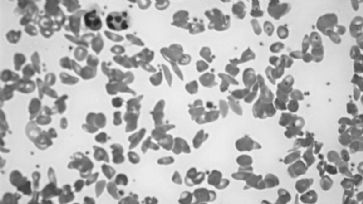

Zwei solche Erbkrankheiten sind die Sichelzellenanämie und die Mukoviszidose, die für jene, die an diesen leiden, schon von früher Jugend an die grausamen Versprechen eines jahrzehntelangen Leidensweges und eines frühen Todes beinhalten.

Beide Krankheiten resultieren in qualvollen Krankheitsbildern und Verkürzen das Leben der Betroffenen um etwa die Hälfte. Opfer der Mukoviszidose werden im Schnitt 37, jene der Sichelzellenanämie 41 Jahre alt.

Doch das Bild sieht anders aus: Die Erforschung der Mukoviszidose hat in etwa das vierfache Budget der Erforschung von Sichelzellenanämie. Die Behandlung von Opfern der Sichelzellenanämie in Notaufnahmen und Krankenhäusern sei zudem vor allem durch Misstrauen gegenüber den Patienten und Ignoranz betreffend der angesagten Behandlung geprägt. Opfer der Sichelzellenanämie können wegen Durchblutungsstörungen extreme Schmerzanfälle erleiden, werden aber vielfach als Pseudopatienten behandelt, die nur versuchten, Schmerzmittel (Opiate) zu schnorren. Für Mukoviszidose-Patienten gibt es dagegen Spezialkliniken und die Stiftungen für die Erforschung dieser Krankheit sind mit Milliarden-Mitteln ausgestattet.

Wenn man sich fragt, aus welchem Grund die Patienten und die Krankheiten so unterschiedlich gehandhabt werden, kann man natürlich verschiedenste Erklärungen suchen. Doch die offensichtlichste ist jene, dass Mukoviszidose eine exclusive Krankheit der Weissen, Sichelzellenanämie eine ist, die in den USA nur Afro-Amerikaner trifft.

Blutbild bei Sichelzellenanämie: Diskriminierte Krankheit. /